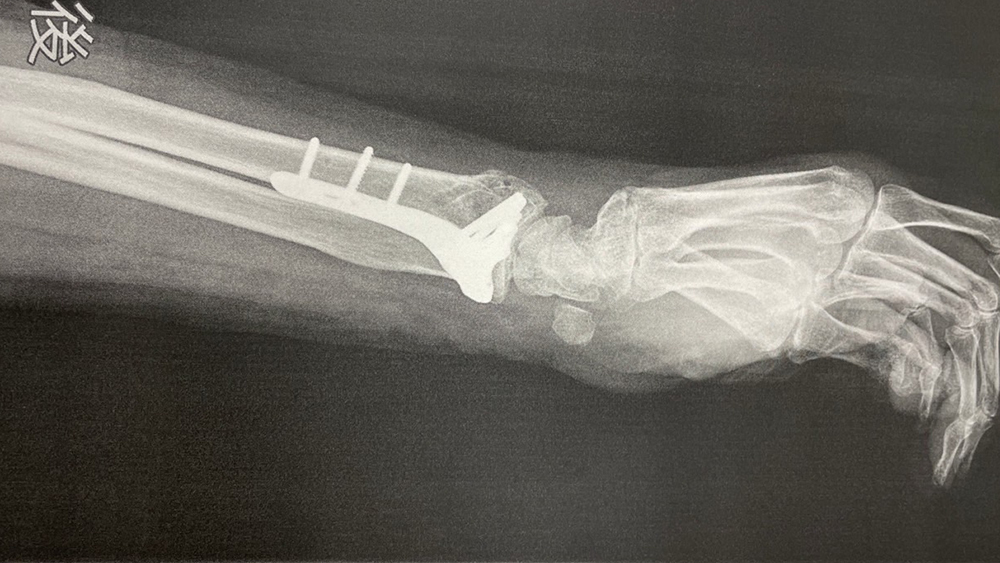

治療には二通りあり、骨がずれていなければ保存療法が選ばれ、骨がずれている場合には手術療法が適応されることがあります。

膝の痛みで踏ん張りがきかず、躓いたときに転倒、手首を骨折してしまいました。はじめは、整形外科のギプス固定だけでしたが、なかなか骨がくっつかず、当院で、超音波治療で早期回復しました。もともとの膝の治療に加え、躓いたときに踏ん張る力である大腿四頭筋の治療、リハビリをすることで、筋肉量、筋力が増え、骨にも適度な負荷を加えることに繋がり、骨密度が増加しました。また、足踏み、つま先を上げるトレーニングと、足を上げやすくする治療で、転倒のヒヤリハットが大幅に減少しました。

以前、躓いた際に右手をつき、骨折した経験があります。そのときは、固定だけで済んでいましたが、今回は同様の怪我で左手を骨折、ボルト固定となりました。ここ数年、躓きやすくなったことと、両手を骨折した影響で未来への不安を感じ、まだ一人暮らしを続けたい思いが強く、躓かないようにしてほしいと来院。細身で背中が曲がっており、治療として、姿勢矯正による正しい重心移動と足を上げやすくして転倒を予防するための治療計画を提案しました。